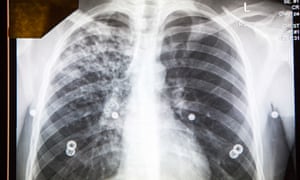

I realised I must have passed the Find & Treat van on a dozen occasions over the years without having the faintest idea that it was a TB eradication machine. Stepping inside I found a small world of nurses, social workers, former TB sufferers, and people having their lungs screened by a radiologist called Jane Knight.

Showing me a pair of lungs on the screen, she described what she was looking for. As it happened, I had been thinking a good deal about lungs that week, not only in preparation for my exploration of TB in London with Story but because I had the day before, had my lungs x-rayed as part of a general health check attached to rheumatoid arthritis. And while I was in the Find & Treat van my consultant at University College hospital actually left a message on my mobile phone asking me to call her.

When I came home that afternoon to think about how TB became the untold story of the city, something extraordinary happened, the coincidence of which I still haven’t quite absorbed. My consultant rang again and told me that, having looked at the x-rays of my lungs, it appeared I had two tumours. They might be malignant, they might be benign. I returned the next day to University College hospital for a CT scan of my chest, and thought, as I lay there, of the many thousands of lungs that Jane Knight and Al Story had examined over the years in their x-ray van.When the results of my scan came back it transpired that the tumours were not cancerous, but the remnants of undiagnosed childhood TB. I had lived with tuberculosis for 40 years, as unaware of the infection as I was of the River Fleet flowing beneath my house. TB was my story too.